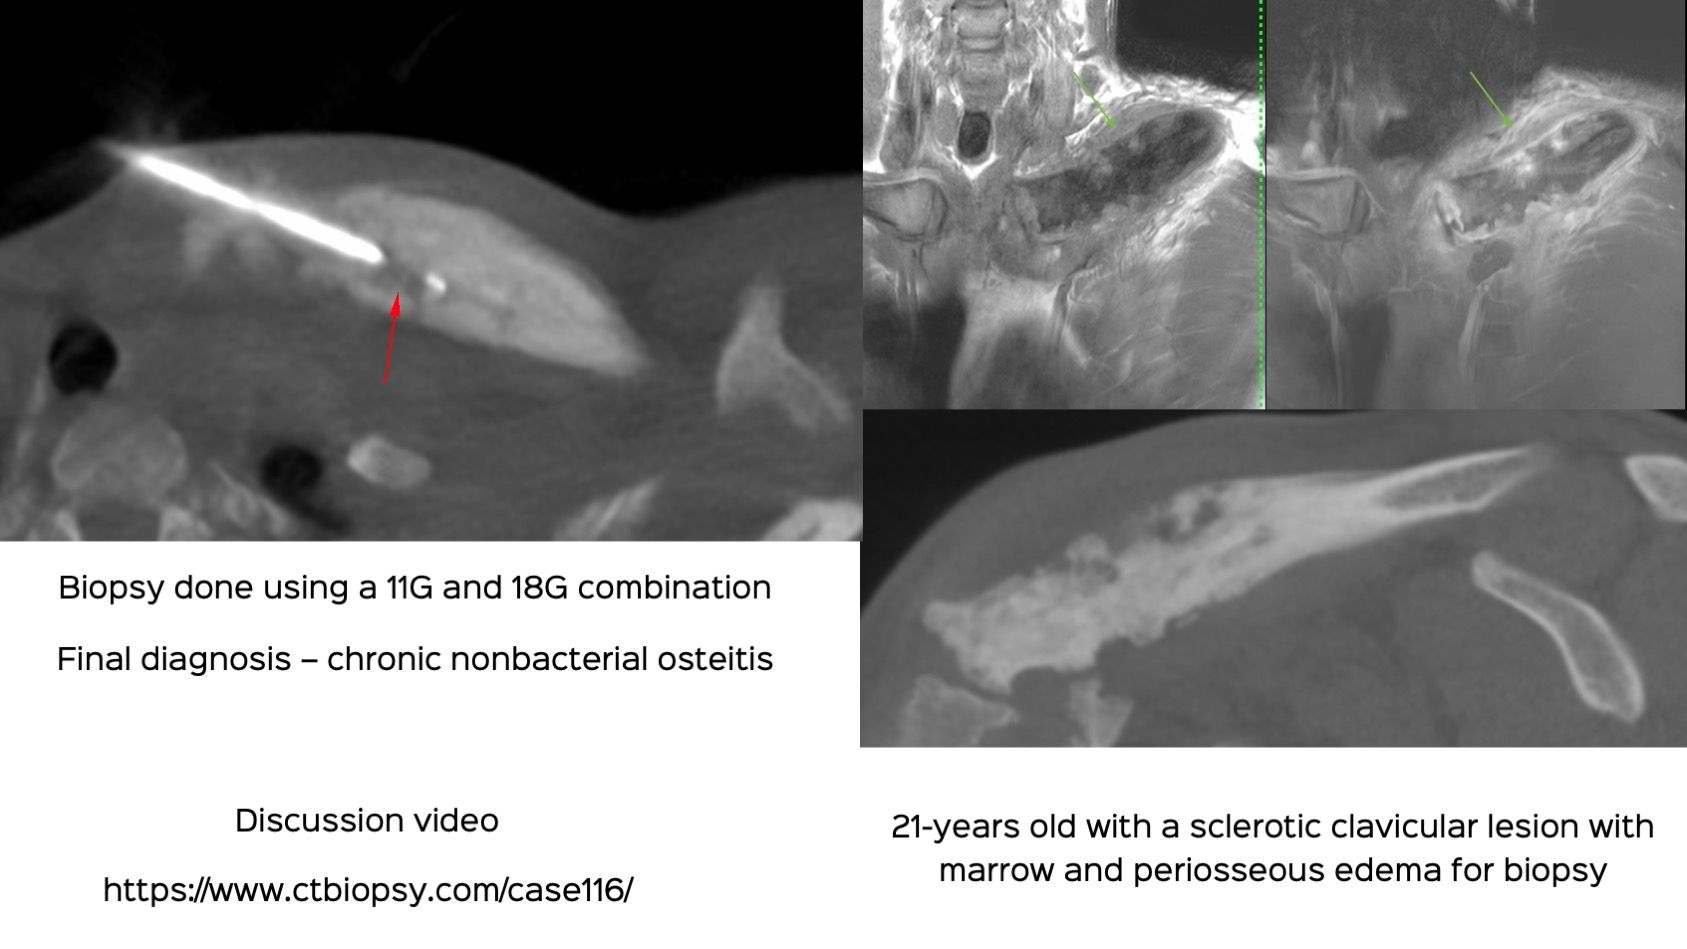

Case 116: Clavicular Lesion Biopsy